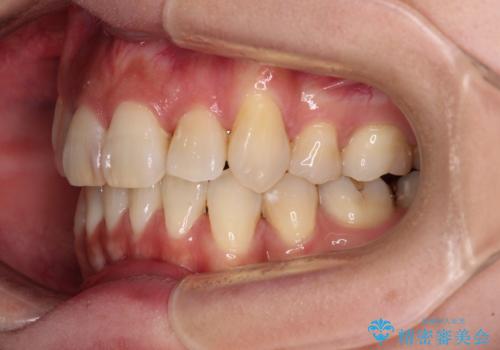

- 1年11ヶ月

デコボコが強い一方で出っ歯ではなかったため、抜歯したスペースを容易に閉じることができ、短期間での治療となりました。